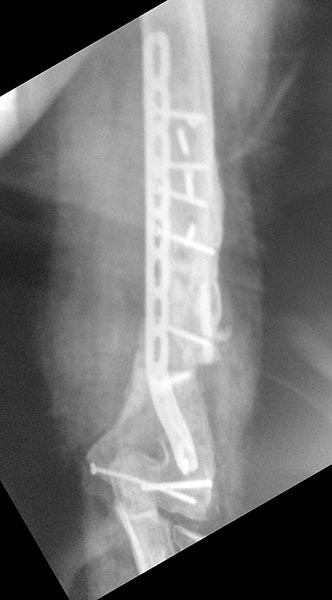

Уважаемые коллеги, хотелось бы услышать вашего мнения по поводу непростого случая несросшегося перелома плечевой кости. Пациент 44года в 2013г закрытый многооскольчатый перелом дистального отдела правой плечевой кости. Остеосинтез пластинами в одной из столичных клиник. В п/о периоде нейропатия лучевого и локтевого нервов, за 10 месяцев лучевой полностью восстановился, локтевой почти - небольшие парастезии в мизинце остались. Обратился ко мне летом 2015г (по совету общего знакомого), до этого обращался в учереждение где был выполнен остеосинтез, но в силу ряда причин не пожелал там оперироваться (кстати предлагалось только удаление металлофиксаторов). Пациент без вредных привычек (разве что переедание), из сопутствующей патологии ожирение (вес 160 кг рост 190см), сахарный диабет (невысокие цифры).В августе 2015г удаление металлофиксаторов, невролиз лучевого нерва, реостеосинтез (той же) пластиной, но в положеном задне-латеральном положении. При операции удалено около 50 куб. металлоза, при ревизии в месте несращения были подозрительные творожистые включения, но кость выглядела здоровой,все многократно промывал антисептиками, иссечены рубцы, края отломков адаптированы друг к другу по типу замка - зона контакта большая, суммарно кость укорочена около 1,5 см. Перед операцией планировал ставить 2 пластину медиально, но до операции консультировался с более опытными коллегами и ставить вторую пластину не рекомендовали, все же заказал, но не поставил... операция заняла в целом 7,5 часов то ли устал, то ли действительно фиксация показалась достаточной учитывая характер сопоставления отломков (ну не суть важно что сделано то сделано). Был установлен дренаж, но наследующий день он забился - удалил, опасаясь инфицирования довольно агрессивно промывал хлоргексидином, на 5 сутки на коже нижней трети плеча по наружной поверхности появился пузырь 10 на 10 см, промывать перестал. Рана зажила первичным натяжением. Дефект кожи после фликтены постепенно заживает (от пересадки кожи пациент отказался). После операции нейропатия лучевого нерва (целостность сомнению не подвергается был выделен весь) за 2 месяца значительная положительная динамика. Иммобилизирован на косынке. В сентябре ниже локтевого отростка появилась небольная безболезненная припухлость по ходу рубца, была вскрыта и получен гной (со слов коллеги я был в отпуске), через 4 дня я видел рану гноя не было отделяемое серозное больше похоже на синовиальную жидкость (предполагаю что идет от локтевого отростка к которому было пришито сухожилие трицепса тисорбом они часто текут по личныим наблюдениям, но не факт...), неоднократно посев роста нет, кровь спокойная, температуре нет соответственно. 2 месяца после операции (22.09.15г) КТ контроль - все стабильно. Две недели назад разрешил иногда снимать косынку но рукой не пользоваться. Неделю назад пациент стал говорить что появился хрукт. Рентген контроль - перелом 2х винтов нестабильность вторичное смещение. Предварительно планирую брать на ревизию удалить винты с проксимального отдела, репозиция остеосинтез и дополнительно медиальная реконструктивная? пластина.

1. По представленной информации не совсем понятен смысл выполненной вами в августе операции. На передне-задней рентгенограмме убедительных признаков несращения нет. Было бы неплохо выложить вторую проекцию - возможно она действительно продемонстрирует несращение. Прикрепленная КТ не читаема (и наверное это КТ за сентябрь). (Кстати желательно уменьшить размер файлов согласно инструкции на сайте - очень долго грузятся).

Пока же кроме варусной деформации, нескольких сломанных винтов и костных наростов (которые можно трактовать как признаки инфекции) на прямом снимке ничего страшного не видно. Такая деформации клинически вряд ли будет играть роль у пациента весом 160 кг.

Может не так хорошо видно, но ВСЕ винты были сломаны и из 7,5 часов 5 ушло на удаление и невролиз, может не так хорошо видно но ВСЕ винты были сломаны, все было в грубом рубцовом конгломерате и металлозе, промывал хлоргекс и бетадином, фликтеной назвал условно потому как предполагаю что из-за выраженного отека и плюс дополнительно накачивал промывая остро появился пузырь отслоивший кожу (как его по другому назвать не знаю), насчет зачем полез, да почему то многие считают что пациенту нужно было ждать пока не сломается пластина, компрессию дал, между фрагментами винт поставил на снимке видно(хотя думаю не стоило он и сломался). И снимок за 6 месяцев до последнего где было только 2 винта сломано выкладываю.

"Может не так хорошо видно, но ВСЕ винты были сломаны..."

- боковая проекция ответила бы на все вопросы относительно показаний к операции.

А снимки сразу после вашей операции позволили ли бы четче оценить выполненный остеосинтез.